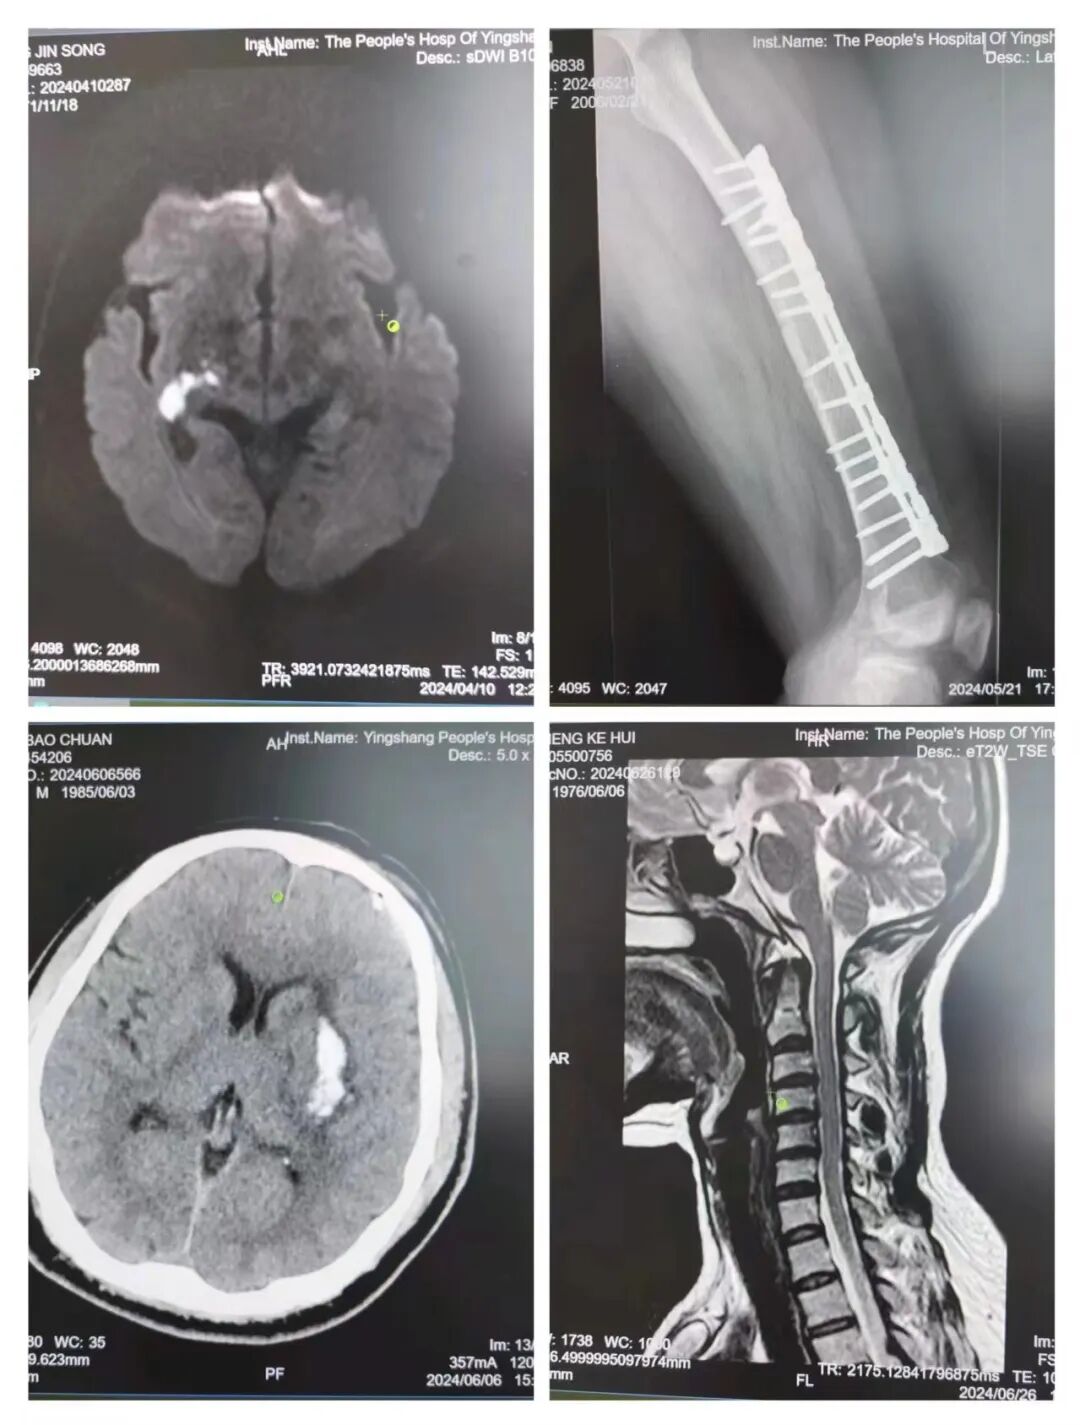

1. 神经系统疾病:如脑卒中、帕金森病、脊髓损伤等,这些疾病常导致患者运动功能受限、平衡感丧失、肌肉萎缩、吞咽及言语功能受损等。

2. 肌肉骨骼系统疾病:包括骨折、关节置换术后、关节炎、颈椎病、腰椎间盘突出症等,这些疾病往往影响患者的日常活动和运动能力。